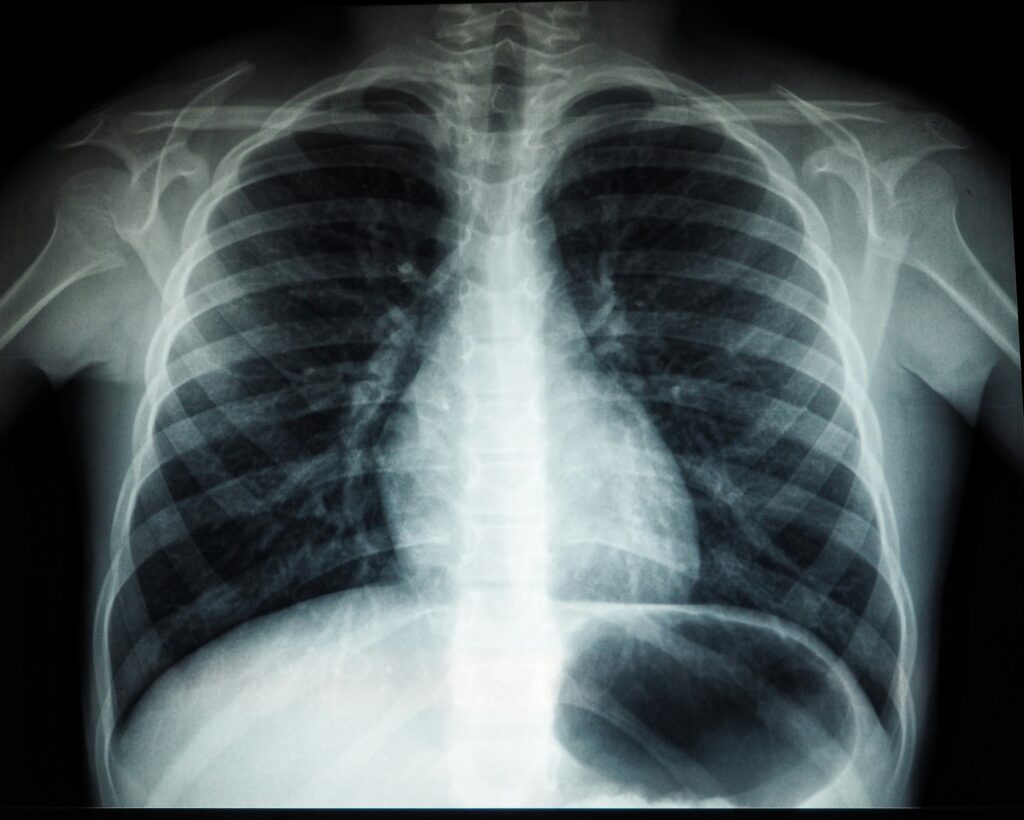

It has been pointed out that “Radiochirurgia Zagreb is the leading speciality hospital in Croatia for the early detection and treatment of cancer, using some of the most advanced technologies in the fight against malignant diseases. Over the past seven years, the hospital has treated more than 10,000 patients and processed more than 90,000 cases, with a special focus on lung, liver and prostate cancer, thereby strengthening its position as a leader in oncology care not only in Croatia, but also in the wider region of Southeastern and Eastern Europe”.